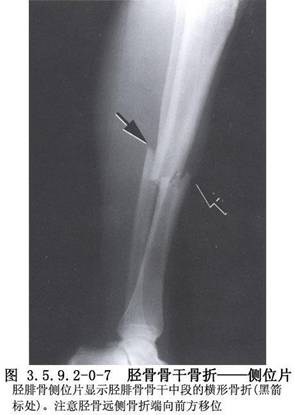

與發生在身體其他部位的骨折一樣,脛骨幹骨折的治療也可分閉合復位外固定,外固定架固定及開放復位內固定三類。隨着內固定材料和技術的不斷髮展及人們對骨折後功能恢復時間及程度要求的不斷提高,開放復位內固定有逐漸增多的趨勢。脛骨幹骨折的影像表現見下圖(圖3.5.9.2-0-5~3.5.9.2-0-7)。